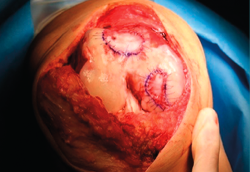

8. The membrane is placed in the lesion and the margins of the former are sutured to the healthy cartilage with Vicryl® 5/0 (Figures 11 and 12).

9. We check that the membrane is well fixed and seal between the stitches with Tissucol® (Figure 13). A waiting period of 3-5 minutes is observed, and the joint is mobilized before closure to check that the membrane does not detach with movement of the joint.